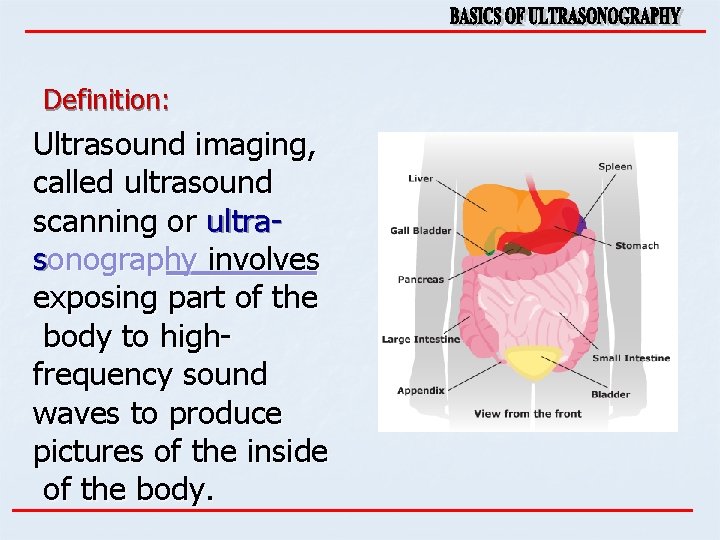

Definition: Ultrasound imaging, called ultrasound scanning or ultrasonography involves exposing part of the body to highfrequency sound waves to produce pictures of the inside of the body.